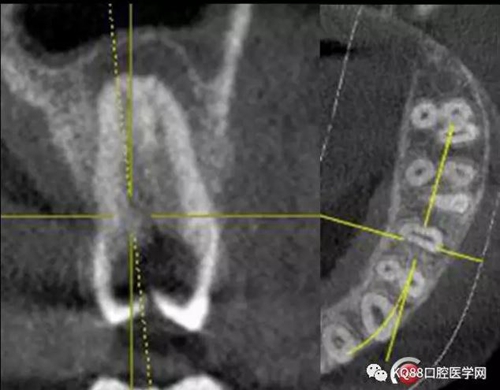

一個(gè)上6,常規(guī)的拍片,同上面的方法,根管口定位,乍一看三個(gè)根管,但是仔細(xì)研究,發(fā)現(xiàn)近中頰根,兩個(gè)根管口的C型根管,心理明了以后開(kāi)始常規(guī)操作。

第一開(kāi)髓后,只看見(jiàn)三個(gè)根管,于是進(jìn)行三個(gè)根管的預(yù)備,然后按照髓底解剖圖,進(jìn)行Mb2探查,近中頰根與腭根連線,遠(yuǎn)中頰根向其做垂直線,一般都在這條線附近,于是我開(kāi)始去髓底白色鈣化,終于找到了Mb2,有鈣化,但是疏通后,到達(dá)根方,于是拍攝插針片。

四個(gè)根管成型,只是近中兩個(gè)根管融合為一個(gè),典型的C型根管。最后開(kāi)始根充,射片。